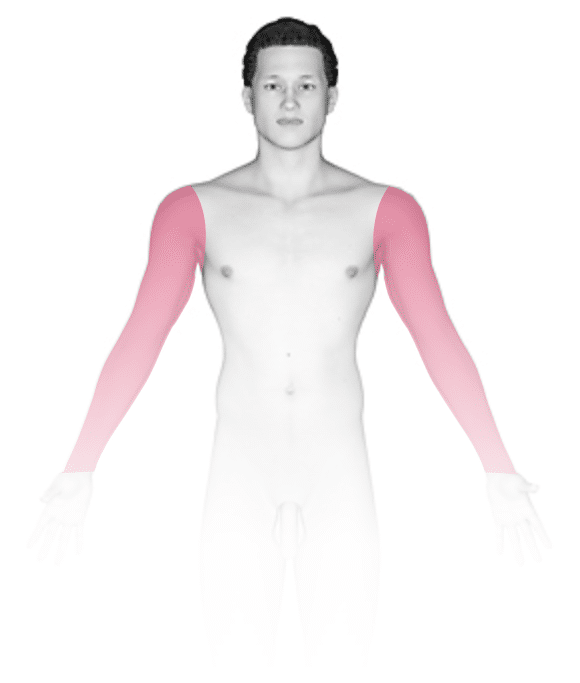

Mucoceles usually occur on the lower lip and inner part of the cheek, as these are frequent areas of mouth trauma, but they can occur anywhere inside the mouth. A mucocele is usually a single bump with a slight bluish or normal skin color, varying in size from 1/2 to 1 inch, and it is soft and painless. A mucocele may appear suddenly, while a mucus-retention cyst may slowly enlarge.